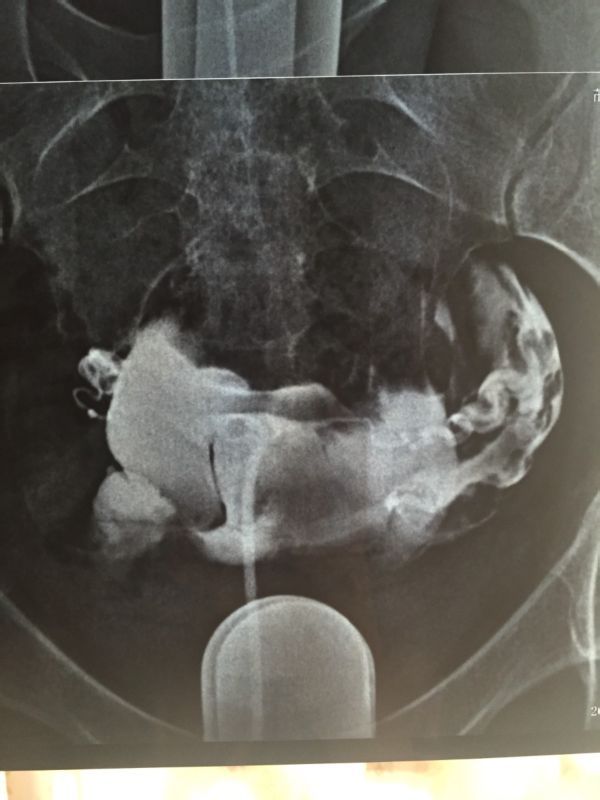

原发性不孕,碘海醇造影,双侧输卵管显示迂曲,伞端见造影剂聚积,造影剂通过双侧输卵管进入盆腔弥散,部 分呈团状显示,考虑:双侧输卵管伞端粘连,不全阻塞,请问要做手术吗?手术成功率高吗?怀孕几率高吗?急盼答复 点击展开 匿名用户 2015-03-29 18:16 为您推荐: 其他回答 你好,如果双侧输卵管不是完全堵塞的话,做手术后怀孕的几率非常大。建议你选择手术治疗,如果害怕手术失败可以选择做试管婴儿。 天使7737 2015-03-29 22:28 相关问题 右侧输卵管部分峡部显影 左侧输卵管走行迂曲,造影剂流速正常,数秒钟后可见中量造影剂弥散入盆腔,涂布 右侧输卵管部分峡部显影 左侧输卵管走行迂曲,造影剂流速正常,数秒钟后可见中量造影剂弥散入盆腔,涂布 右侧输卵管部分峡部显影 左侧输卵管走行迂曲,造影剂流速正常,数秒后可见中量造影剂弥散入盆腔,涂布欠